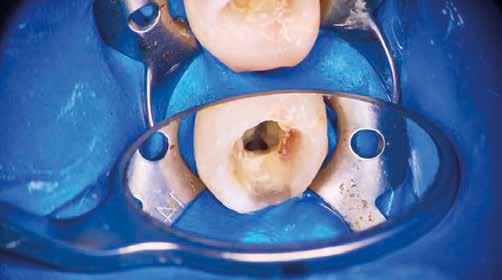

Helyi érzéstelenítést követően kofferdám került felhelyezésre, majd az izolálást folyékony kofferdám felvitelével (RUBBER-DAM liquid, CERKAMED) erősítettük meg (2. ábra). Ezt követően az ideiglenes tömést eltávolítottuk és a pulpakamrát desztillált víz, valamint ultrahangos hegyek segítségével aktivált 5,25%-os NaOCl oldattal megtisztítottuk (3. ábra). Az első mesio-bukkális (MB1), a diszto bukkális (DB) és a palatinális (P) gyökércsatorna átjárható volt, ezért először egy C-PILOT tű (VDW) és egy elektromos apexlokátor (E-PEX, Eighteeth) segítségével ezekben a csatornákban a munkahossz meghatározásra került. Ezután a gyökércsatornákat nagyjából az eredeti munkahossz kétharmadáig

reciprok mozgást végző gépi gyökérkezelő tűkkel feltágítottam (#25/.07 Perfect Shape; Shenzhen Perfect Medical Instruments). Ezt követően az MB2 gyökércsatorna bemeneti nyílását fedő dentint egy gyémánt borítású ultrahangos fej segítségével eltávolítottam (ED3D, Woodpecker). A terület vizsgálatát követően észleltem, hogy az MB1 és MB2 csatornákat egy vékony résszerű nyílás (isthmus) köti össze. Az MB2 csatornának csak a koronális harmadát volt lehetséges kézi eszközök segítségével megmunkálni (4. ábra). Az MB csatornák között lévő rést 2 mm mélységben az előzőleg használt gyémánt borítású ultrahangos fejjel eltávolítottam (5. ábra)

Az átöblítés során a roots magazin egy korábbi számában (2/2022) bemutatott protokollt alkalmaztam (Less-Prep Endo enhanced irrigation protocol). Az átöblítőszer aktiválása SkyPulse lézer (Fotona) segítségével AutoSWEEPS (shock wave enhanced emission photo-acoustic streaming) módban történt. Ennek köszönhetően az MB2 csatorna középső harmada is átjárhatóvá vált a C-PILOT tűk számára. Ezt radio-

lógiai felvételek segítségével is igazoltuk (6–7. ábra). Az MB1 és MB2 csatornák között az átöblítőszerek szabad áramlását észleltük. A gyökércsatornákat crown-down technika szerint a C-PILOT és Perfect Shape gépi gyökérkezelő tűkkel megmunkáltuk, de időhiány miatt a megmunkálás teljes munkahossznál rövidebb mélységben történt. Az ülés végén a fogat kompozitból készült ideiglenes tömés segítségével zártuk és a pácienst egy másik időpontra visszarendeltük.